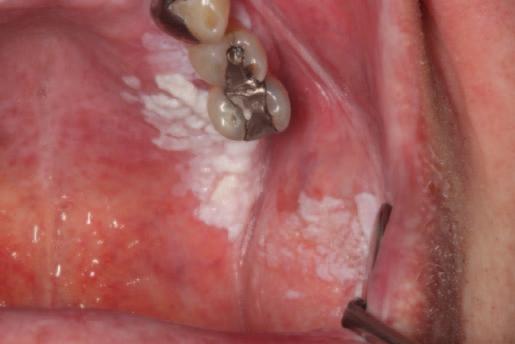

Oral leukoplakia: an update for dental practitioners

Précis: This narrative review presents an evidence-based overview of oral leukoplakia, discussing its diagnosis and treatment, and the challenges involved in its management.

Abstract

Statement of the problem: Oral leukoplakia is a common mucosal pathology frequently encountered in general dental practice, which belongs to a group of conditions known as oral potentially malignant disorders. This inferred risk of progression to oral squamous cell carcinoma (OSCC) warrants an understanding of the aetiology of this condition, its clinical presentation, and how patients diagnosed with oral leukoplakia are managed in both general and specialist care practices.

Discussion: The aetiology for oral white patches can range considerably from innocuous frictional keratosis to OSCC. A thorough history and clinical examination should precede referrals to secondary care, with the elimination of risk factors a priority. In cases where white patches are suspicious, or remain despite managing known risk factors, prompt referral to a specialist centre is warranted. Despite the extent of research in this field, controversy remains in oral leukoplakia management and there is currently no agreed international consensus. Therefore, management is primarily governed by local contemporaneous guidelines, and is based on the most reliable predictor of malignant transformation: the grade of dysplasia. Despite various treatments, oral leukoplakia may still undergo transformation to malignancy.

Conclusions: General dental practitioners (GDPs) are the healthcare practitioners best placed to detect oral leukoplakia on a daily basis, given the volume of patients encountered from various backgrounds. An understanding of the causes and presentation of oral leukoplakia will allow GDPs to recognise this entity in practice, and facilitate further management and treatment in a bid to prevent transformation.

(Table 1). The term OPMD refers to any oral mucosal abnormality that is associated with a statistically increased risk of developing oral cancer.1 Given the risk of malignant transformation associated with leukoplakia, it is imperative that general dental practitioners (GDPs) recognise oral leukoplakia and understand the appropriate management of this condition.

Aetiology

The development of oral leukoplakia appears to be multifactorial in nature. However, the definitive cause is unclear. Smoking has been identified as the predominant risk factor, with oral leukoplakia six times more common in smokers.2 Alcohol is recognised as an independent risk factor for oral leukoplakia.3 However, its aetiological role is less clear in oral leukoplakia than in OSCC. Oral leukoplakia also arises in non-smokers and non-alcohol drinkers, suggesting a potential genetic predisposition.4 Betel quid is a significant aetiological factor in Southeast Asia and is responsible for the increased prevalence of oral leukoplakia in this region.

Clinical presentation

Oral leukoplakia can affect any part of the oral mucosa, either as solitary or multiple white patches. The sites most commonly affected include the lateral and ventral tongue, buccal mucosa, and floor of the mouth, the latter site being frequently affected in populations with a high prevalence of smoking.6

Oral leukoplakia may be subclassified into homogeneous and non-homogeneous forms. Homogenous oral leukoplakia (Figure 1) is characterised by a predominantly flat, uniform, often well-demarcated white patch, with a consistent surface topography, and it usually lacks symptoms.1 When homogenous oral leukoplakia is found on the floor of the mouth, it can have a distinctive ebbing tide appearance (Figure 2).

The non-homogeneous form is any white patch that deviates from the above.